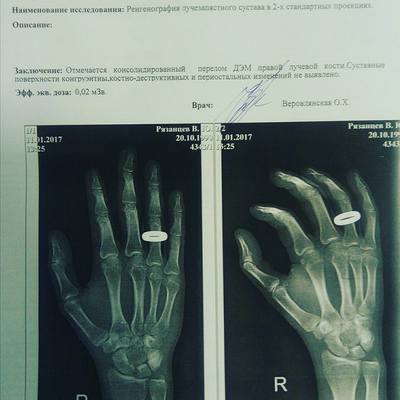

Родился 20 октября 1986 года в Ростове-на-Дону.